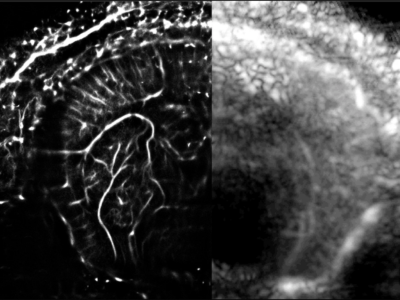

No 13 | Dans les profondeurs de l’embryon de souris

No 21 | Une feuille tombée du petit cerveau